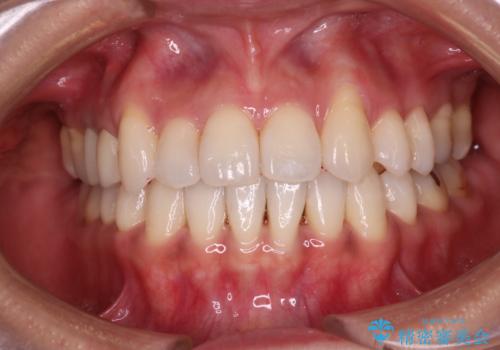

[セラミック治療] 前歯の審美治療に伴う矯正治療